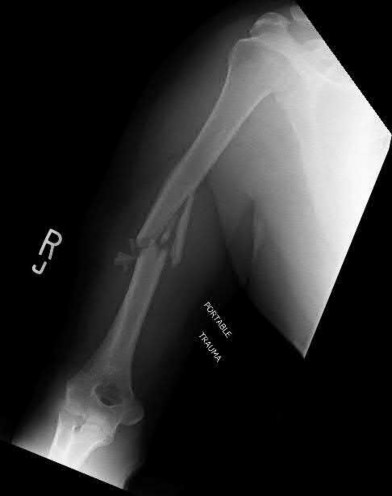

Figure A shows a radiograph of a 19-year-old male with an isolated shotgun injury. On physical examination, he has a 3 cm wound over the posterolateral aspect of his arm. In addition, he has weakness with wrist and finger extension, but no sensory deficits. The patient has received tetanus prophylaxis and antibiotics in the emergency department. What would be the next best steps in treatment?

This patient has sustained a shotgun blast to the midshaft humerus. The next best step would be irrigation and debridement, and external fixation of the fracture.

Shotgun injuries are typically treated as open fractures, whereas low-energy gunshot wounds are treated as closed fractures. The initial operative treatment of shotgun wounds should include irrigation and debridement and stabilization with external fixation. The goal of treatment is to stabilize the severe soft-tissue injury and bone loss, as well as to aggressively debride devitalized tissue and gross contamination.

Dougherty et al. reviewed gunshot fractures to the humerus. They report that

peripheral nerve injuries are relatively common with these injuries, with a more common incidence in distal injuries than proximal.

Joshi et al. looked at low velocity gunshot fractures to the humerus. They found that these injuries can be safely treated as closed fractures with local wound care, fracture brace and oral antibiotics. The time to union was similar in the non-operative and open treatment group.

Berick et al. examined the indications for nerve exploration with humerus gunshot fractures. They recommend continued observation of isolated nerve palsies associated with gunshot fractures of the humerus. However, consider early nerve exploration of palsies when associated with a concomitant vascular injury.

Figure A shows a high velocity shotgun fracture to the left humerus with retained buck fragments. Illustration A shows a similar injury stabilized with external fixation.